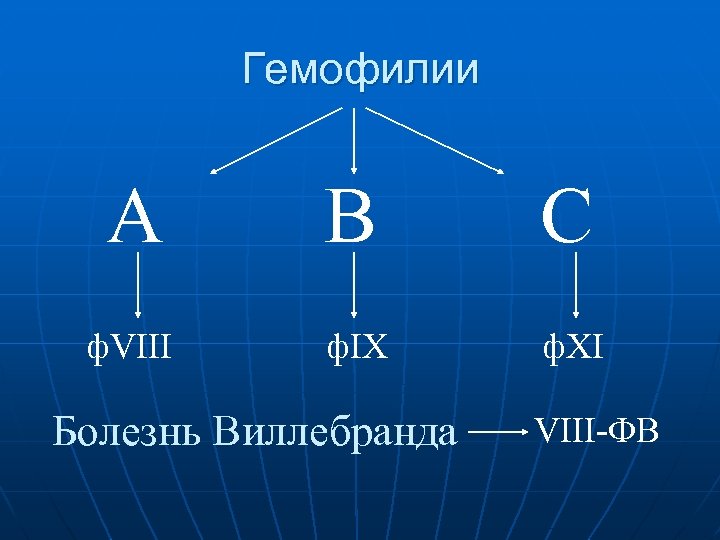

Нарушения коагуляционного звена гемостаза n Наследственные гипокоагуляции: – Гемофилия А – 90% (ф. VIII) в т. ч. Болезнь Виллебранда – 9 -18% (ф. VIII-ФВ) 96 -98% – Гемофилия B – 6 -13% (ф. IX) – Гемофилия С – 1 -2% n (ф. XI) Приобретенные коагулопатии: – Нарушение синтеза факторов системы гемостаза – Укусы змей, насекомых – Отравления и пр.

Гемофилии А В С ф. VIII ф. IX ф. XI Болезнь Виллебранда VIII-ФВ